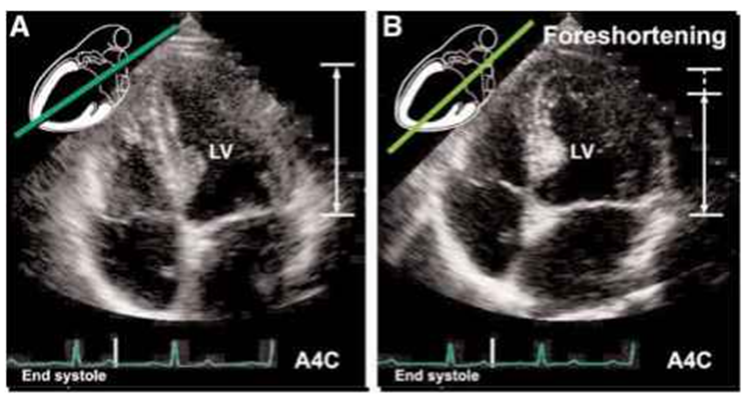

3. Apical View(5,4,3,2 chamber view)

심장을 아보카도 자르듯(?) 자른 단면이라고 생각하면 된다.

심첨부에 probe가 잘 가서 최대한 길게 optimal view를 잘 잡았다면,

같은 부위에서 probe를 회전시킴으로 aorta가 있는 5 chamber,

심방2개 심실2개가 보이는 4 chamber, LV & LA & aorta가 있는 3chamber,

LV 와 LA만 있는 2 chamber를 찍을 수 있다.

LV의 기능, LA크기, doppler를 통한 diastolic function, stenosis parameter,

regurgitation severity 확인 및 doppler측정 등이 가능한 view 이다.